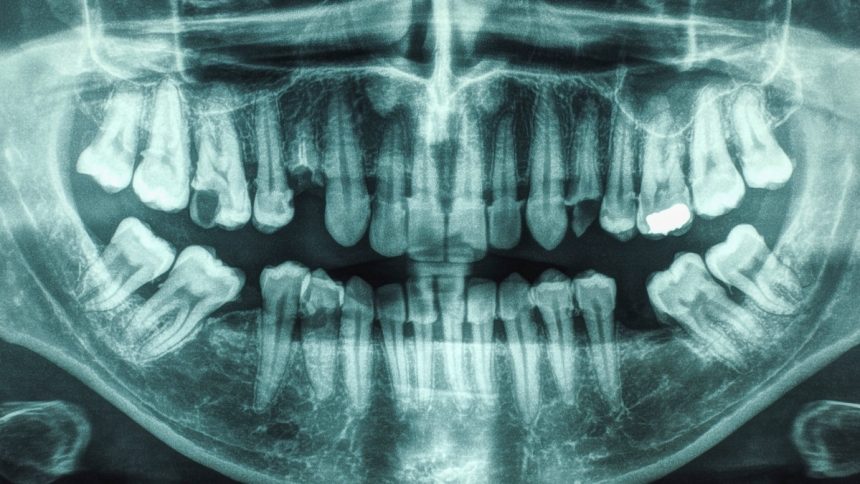

Research has long shown a connection between oral health and overall well-being, with conditions like dementia and diabetes being linked to poor oral hygiene. A recent study has now revealed that individuals with both gum disease and tooth cavities are at a significantly higher risk of stroke.

Past studies have individually associated gum disease and cavities with a higher risk of stroke, but few have examined the impact of having both conditions simultaneously. Led by a team from the University of South Carolina, this new study focused specifically on individuals with periodontal disease and dental caries.

While the study only establishes an association, previous research suggests that inflammation and oral bacteria can contribute to cardiovascular issues by spreading to other parts of the body. Oral bacteria have been found in arterial plaques, which can lead to the formation of clots and potentially trigger ischemic strokes.